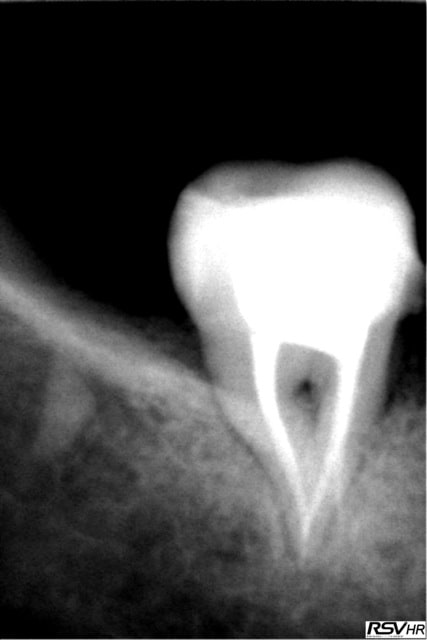

2 retraitements endo sur 45 46.

2 m85na9 - Eugenol

3 j2ewih - Eugenol

4 mbyxz8 - Eugenol

1 ojgvk3 - Eugenol